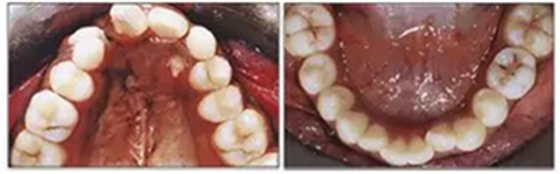

咬合關(guān)系:右側(cè)磨牙有II類關(guān)系傾向,尖牙關(guān)系II類;左側(cè)磨牙關(guān)系完全I(xiàn)I類,尖牙關(guān)系I類。上頜雙側(cè)反合,中線稍有偏離。覆合、覆蓋減少。上頜中切牙向腭裂側(cè)旋轉(zhuǎn),上頜右側(cè)尖牙頰側(cè)異位萌出,雙側(cè)乳尖牙仍存在?;颊呱项M弓嚴(yán)重?fù)頂D(擁擠度約10mm),下頜弓輕度擁擠4mm(擁擠度約4mm)(圖1 ;圖2)。牙周檢查良好。